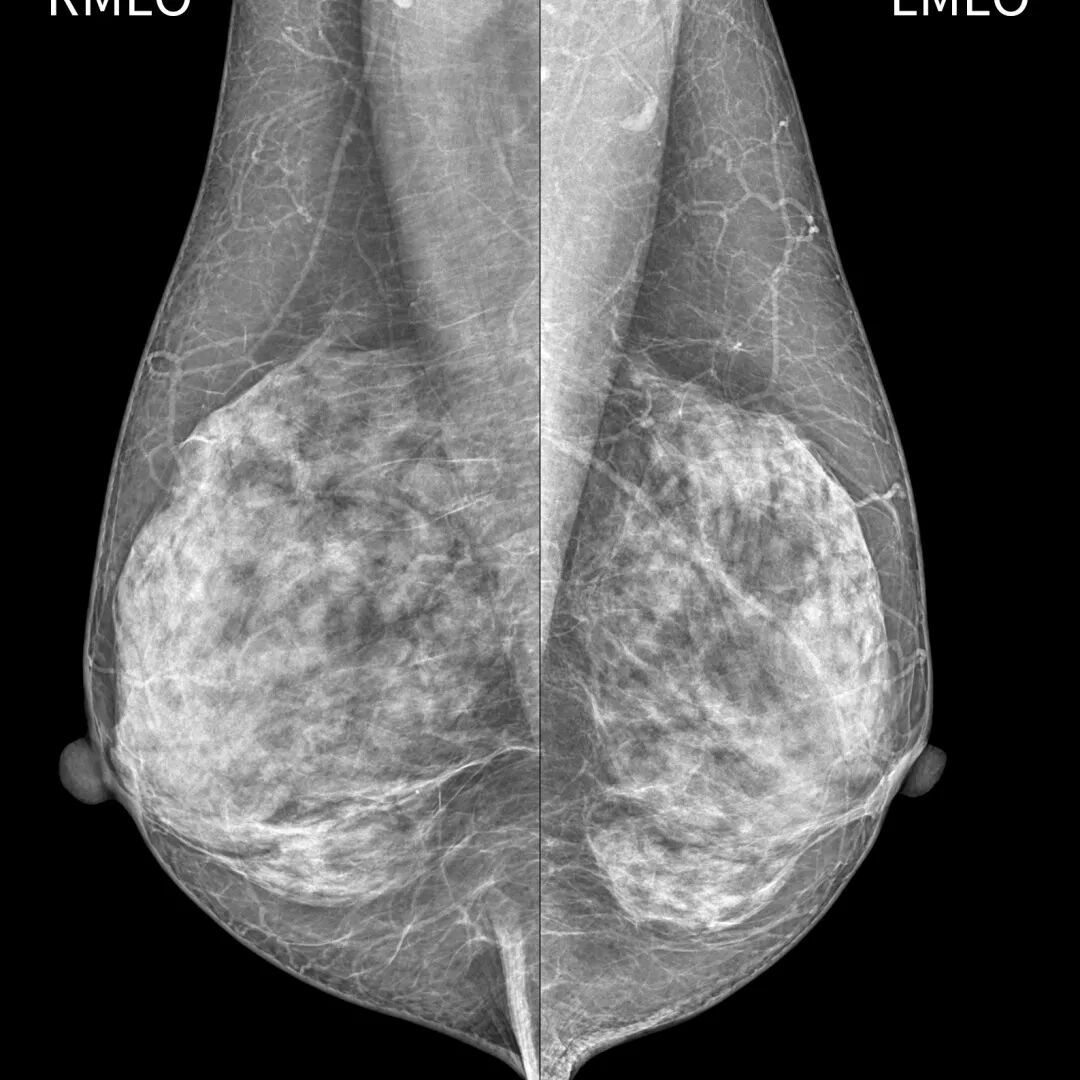

检查样片

深圳蓝影Luna mini全数字化乳腺摄影系统是通过低剂量乳腺X线拍摄乳腺的高端数字乳腺钼靶机。它使用全新大尺寸平板探测器数字成像技术,满足各种尺寸乳腺摄影需求,提高乳腺摄影对低能量X线的吸收率,像素尺寸更小,空间分辨率更高,优质的数字图像让再细微的病变也无所遁形。

该设备能够在乳腺癌的最早期发现病灶,甚至是病灶还处于不典型增生或者原位癌阶段就能诊断发现,能高清晰显示乳房内小于1厘米的结节性病灶,可敏感发现乳腺的微小钙化,清晰“捕捉”早期恶性乳腺肿瘤,并可准确定性、定位,真正做到早期发现、早期诊断、早期治疗的效果,更好地位广大患者服务。